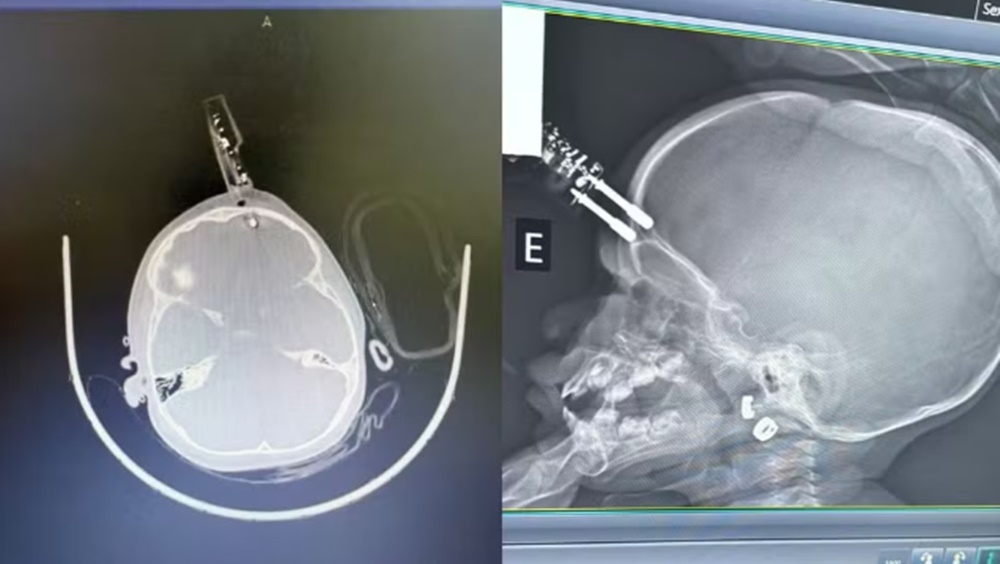

Segundo o especialista, a bebê estava com o carregador na mão no momento da queda, e o objeto perfurou a região frontal do crânio, próximo ao olho.

“O maior risco, do ponto de vista neurológico, é o trauma e a lesão cerebral. O objeto atravessou o crânio, ficou alojado no cérebro, e isso pode provocar hemorragias”, detalhou.